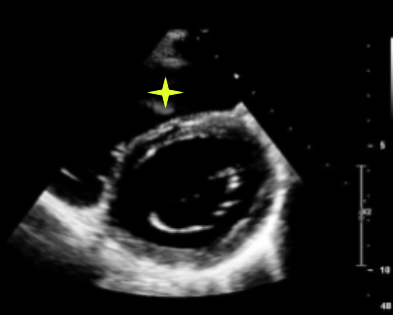

grade 3 restrictive (fuses with valsalva)